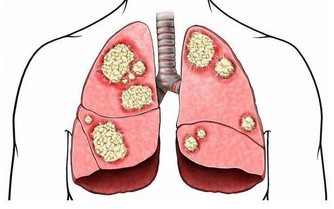

中老年人(45歲以上),由於身體機能的下降和免疫能力逐漸降低,成為我國發病率最高的人群。同樣,也是患癌風險最高的人群。而我國,發病率和死亡率最高的癌症,當屬肺癌!所以,提防肺癌的發生是當務之急!有這「五個信號」的人們,要及時到醫院做檢查,以免耽誤治療!

腫瘤生長於管徑較大、對外來刺激落敏感的段以上支氣管黏膜時,可產生類似異物樣刺激引起的咳嗽,典型的表現為陣發性刺激性乾咳,一般止咳藥常不易控製。由於腫瘤組織血供豐富,質地脆,劇咳時血管破裂而致出血。肺癌咳血的特徵為間斷性或持續性、反覆少量的痰中帶血絲,或少量咯血,偶因較大血管破裂導致難以控製的大咯血。

肺癌所致的發熱原因有兩種,一為炎性發熱,癌腫瘤生長時,常先阻塞段或支氣管開口,引起相應的肺葉或肺段阻塞性肺炎或不張而出現發熱,但多在38℃左右,很少超過39℃。

二為癌性發熱,多由腫瘤壞死組織被機體吸收所致。